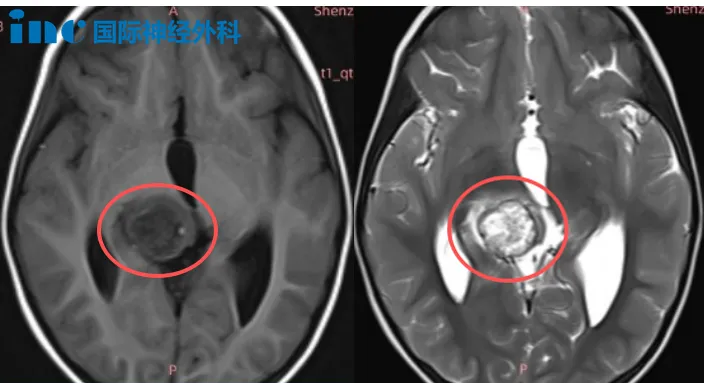

那么,面对这一难题,他们是如何做出决定的呢?近期,巴教授中国行中,又遇到一位这样的小朋友。年仅4岁的女孩果果,连续摔倒后检查发现右侧丘脑占位性病变,大小约22mm×21mm×19mm;邻近中脑左份及中脑导水管受压。果果目前虽然没有明显症状,但还是令父母忧心不已,这个是什么性质的病变?她要不要手术,如果巴教授来手术,手术风险有哪些?小小的果果才14kg能否承受这么大的开颅手术……

巴教授表示:由于肿瘤体积较大并伴有明显水肿,目前的治疗选择是手术。因为如果现在盲目进行化疗,没有确切的病理诊断,是没有意义的——我们并不知道这是什么类型的肿瘤。而对于一个4岁的女孩来说,单独放疗也是不可取的方案。

因此,首要步骤是进行手术,以取得肿瘤组织,获得明确的病理诊断,并进行基因检测。这样我们才能非常准确地判断下一步是否需要额外的治疗。另外,单纯等待或观察也是不可行的,因为存在三个主要原因:肿瘤体积大、水肿明显以及合并脑积水。